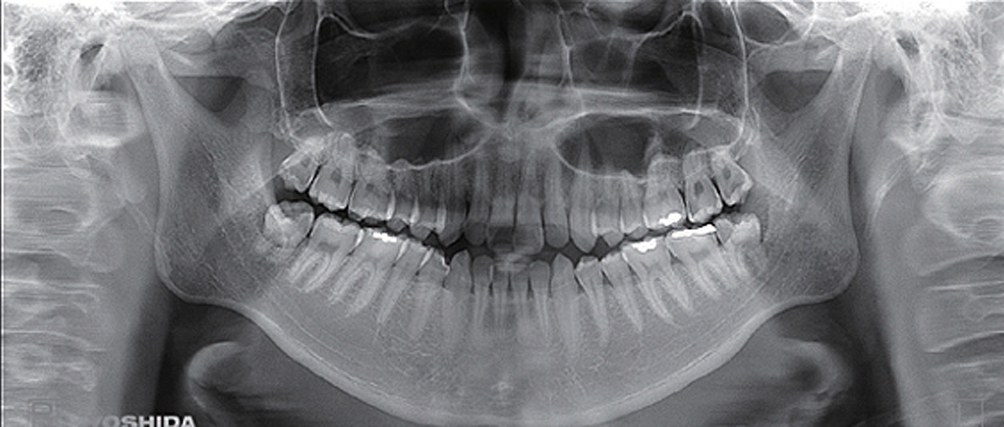

パノラマレントゲン撮影

写真引用:株式会社ヨシダ

パノラマ撮影は横に長くお口全体を映すもので、お口全体の骨、歯の根、顎の状態を一枚で確認できるレントゲンです。親知らずや歯の根っこの膿、顎の骨の異常なども把握でき、幅広い診断の基礎となります。